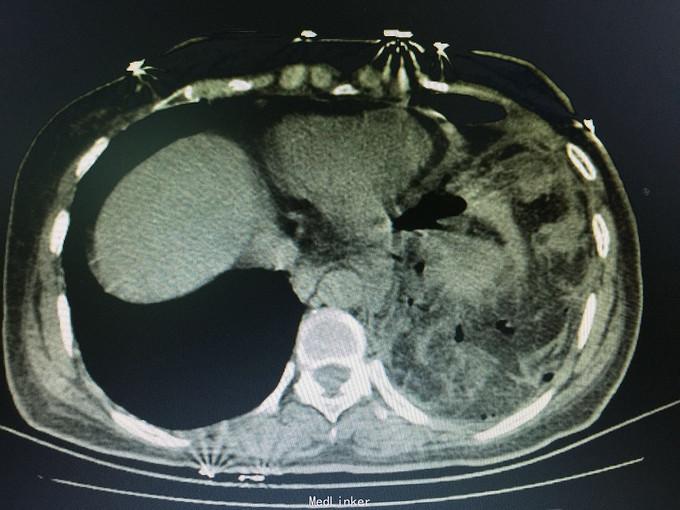

女,41岁, 主诉:腹部胀痛伴不排便、不排气1周, 现病史:一周前无诱因开始腹部胀痛,逐渐加重,以左上腹明显,不排便,不排气,恶心,呕吐数次胃内容物,在当地医院抗炎治疗不见好转,今排腹部平片诊断为“肠梗阻”,来诊。

一般状态可,腹部平坦,未见肠型及蠕动波,脐周压痛,左上腹明显,无腹肌紧张,未及包块,移动性浊音阳性,肠音2次/分。 辅助检查:全腹CT:腹部肠管明显扩张,积液,左侧膈肌局部缺损,腹腔内肠管及系膜组织疝入胸腔。

诊断:膈肌疝,疝内容嵌顿,肠梗阻 处理:手术治疗。

讨论:年轻患者膈肌疝不常见,尤其疝入肠管引起肠梗阻病例更少见;追问病史,该患3年前被刀刺伤左侧季肋部,在外院住院观察,因未见脏器损伤1周后出院,现在考虑为膈肌损伤。